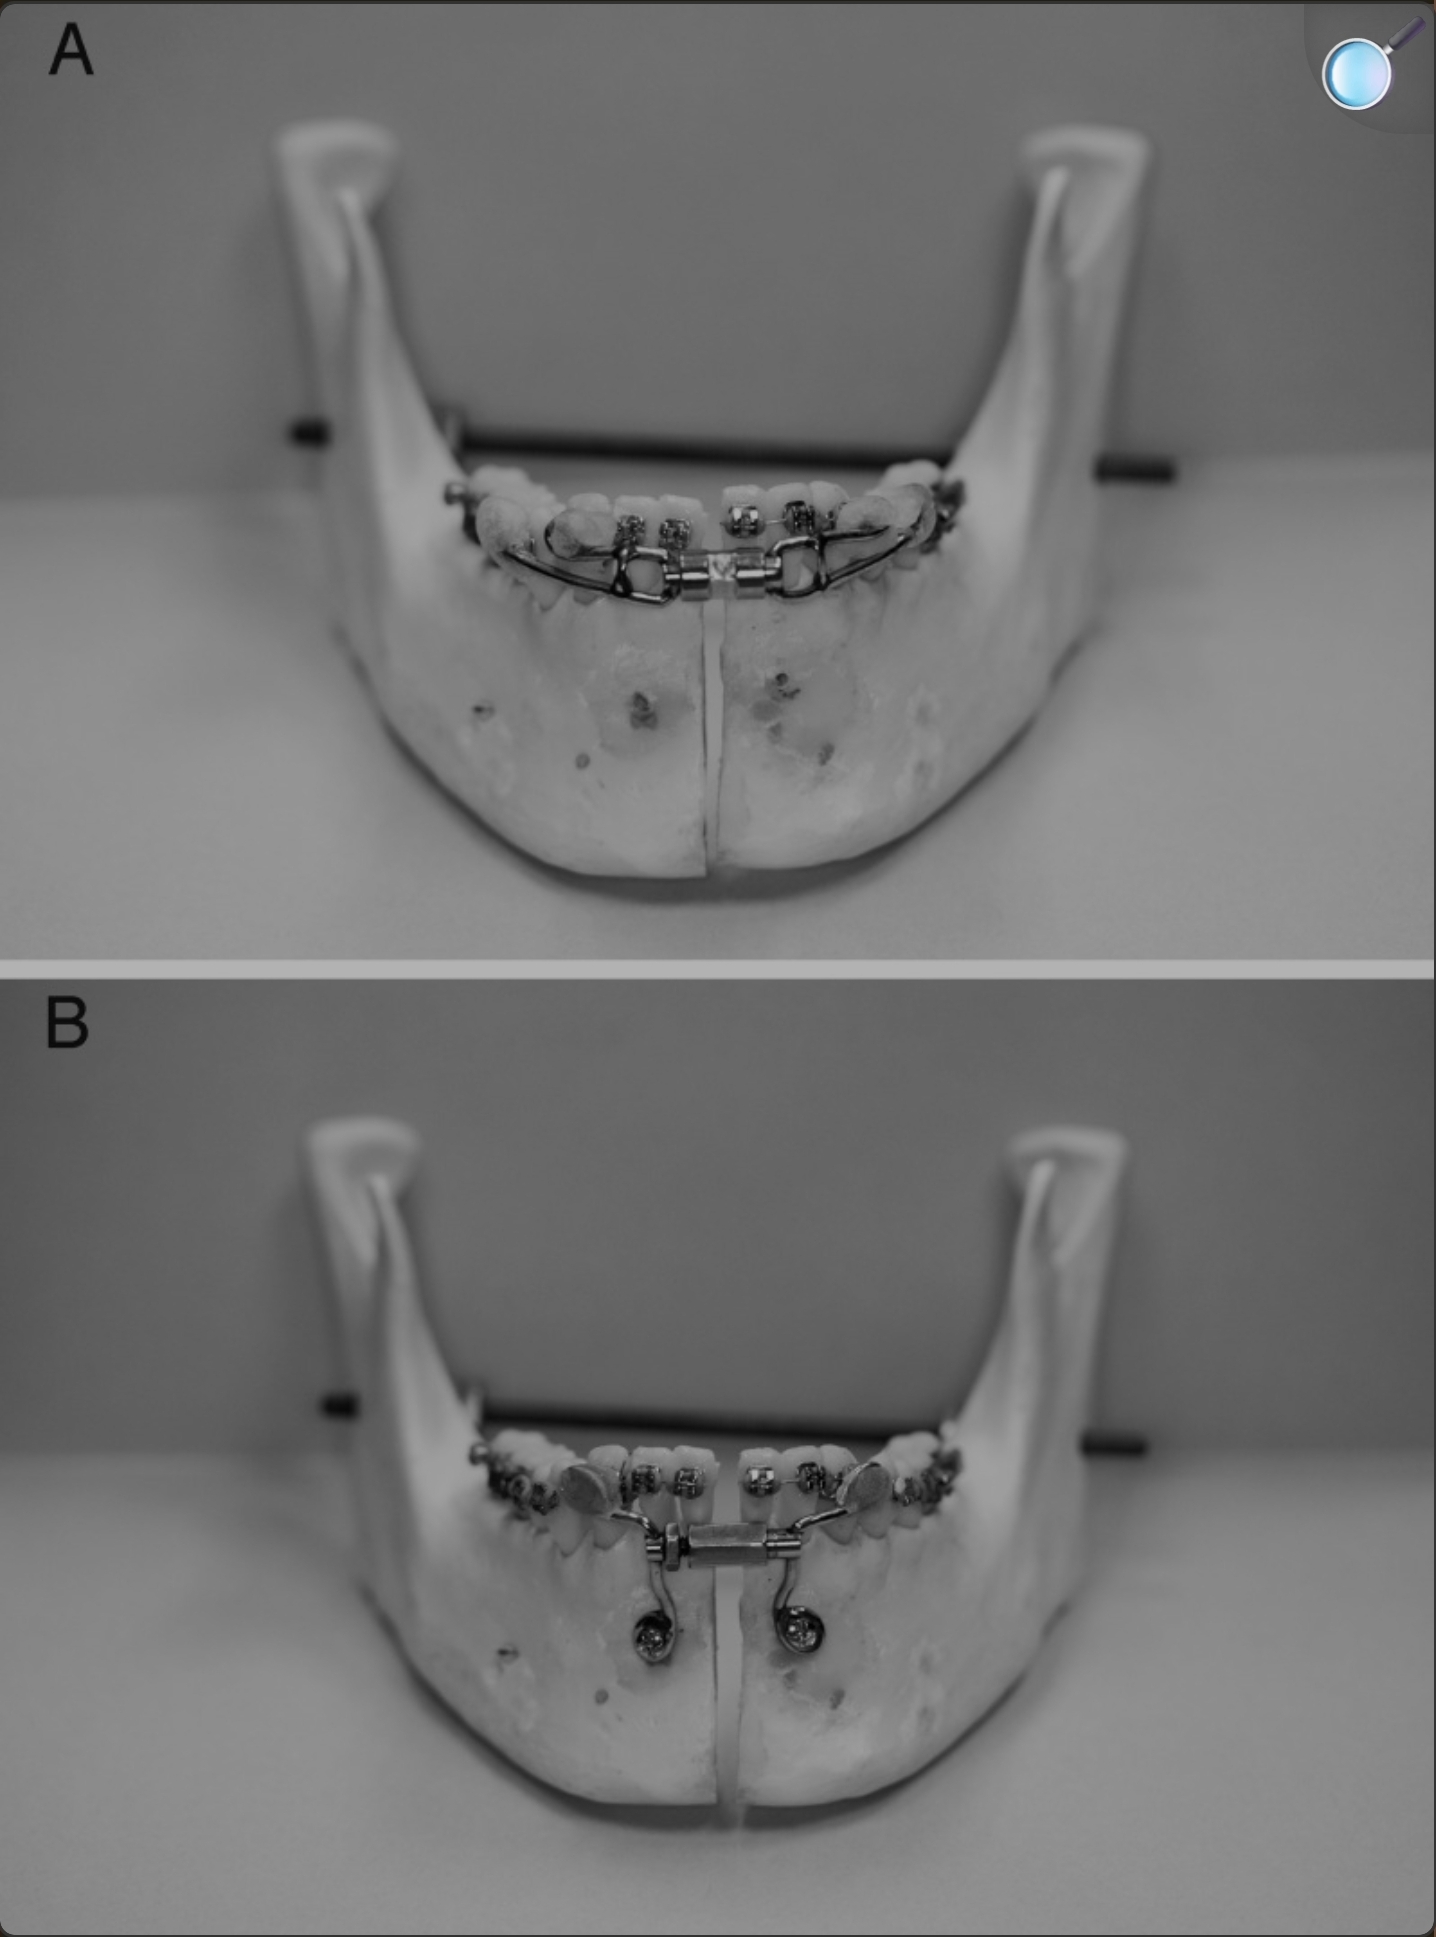

Pictures of his old and new implants have been attached. As always I'm happy to answer questions regarding the thoughts behind certain design choices or anything else. Cheers

Old silicone wraparound:

Old silicone wraparound: